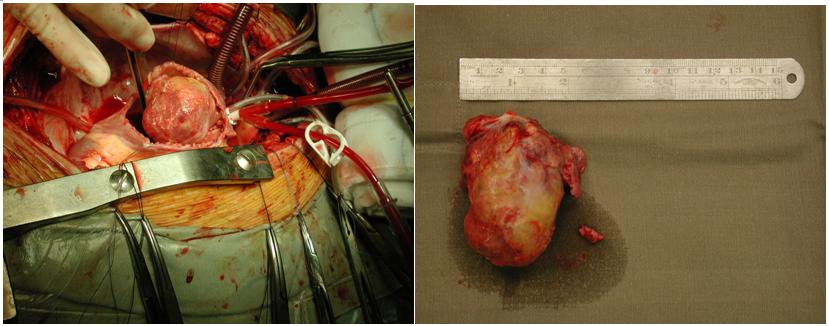

Six days after admission, he still complained of mild haemoptysis. Fever kicked up to 38.5ºc. He developed type I respiratory failure and required 50% of oxygen supplement. Haemoglobin level dropped to 7.7g/dL. CXR was repeated and showed increasing alveolar and nodular shadows(Fig.2). Computerized tomography for thorax with contrast was arranged which found a 4 x 5.5 cm filling defect in right atrium (Fig 3).

There was a large non-gelatinous tumour, arising from right atrium near the superior vena cava entry (Fig.4). Both lungs were found to have patchy consolidation and collapsed changes. There was blood stained pleural effusion in both pleural cavities and a straw colored pericardial effusion.

Concerning the imaging modalities, chest radiograph is useful in identifying the metastatic lung lesions. The features include multiple nodules, linear infiltrations, pleural effusion, diffuse alveolar shadow or pneumothorax.5 Contrast CT scan of thorax can identify the intracardial filling defect which has low attenuation. The metastatic lung lesions can be either nodular or cystic.6 Two dimensional echocardiogram and MRI scan offer no more specific findings. Confirmatory diagnosis still relies on tissue biopsy.